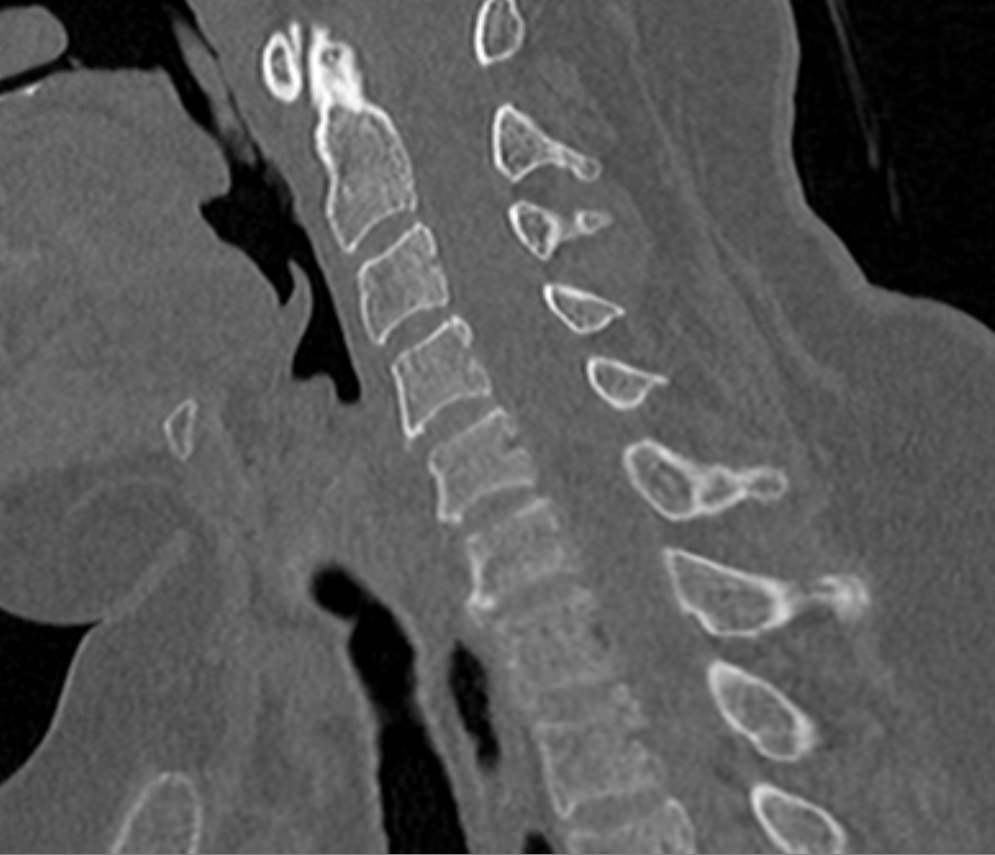

Мультиспиральная компьютерная томография является одним из наиболее информативных методов диагностики дегенеративно-дистрофических заболеваний, травматических, воспалительных изменений, а также опухолевых процессов позвоночника. Методика предусматривает использование рентгеновского излучения для получения детализированных снимков костных структур позвоночника, межпозвонковых суставов и межпозвоночных дисков.

При подозрении на распространенный процесс с поражением различных уровней позвоночного столба показано проведение мультиспиральной КТ трех отделов позвоночника.

В клинике «Доступная медицина» установлены современные мультиспиральные компьютерные томографы экспертного класса TOSHIBA AQUILION в различных модификациях (64-срезовый и 128-срезовый), на которых выполняются комплексные обследования позвоночника, включая одномоментное исследование несколько отделов. Аппараты производят сканирование с помощью рентгеновских лучей, делая тончайшие срезы с шагом от 0,5 мм, затем с помощью компьютерных программ полученные данные преобразуются в изображения трехмерного формата, что обеспечивает точность и достоверность диагностики.

С помощью мультиспиральной КТ можно диагностировать:

- дегенеративно-дистрофические заболевания позвоночника (остеоартроз, спондилез, деформирующий спондилоартроз);

- травматические повреждения позвоночника (компрессионные и оскольчатые переломы);